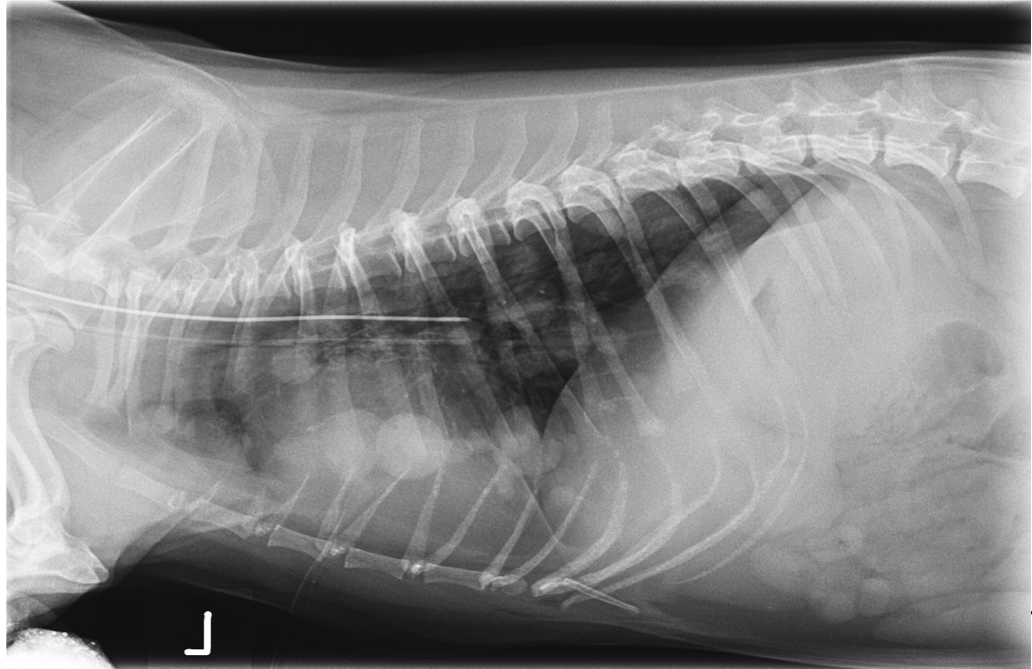

Which lung pattern is shown here?

A

Alveolar

This is limited to the diaphragmatic lung lobes.

There is border obliteration of the diaphragm.